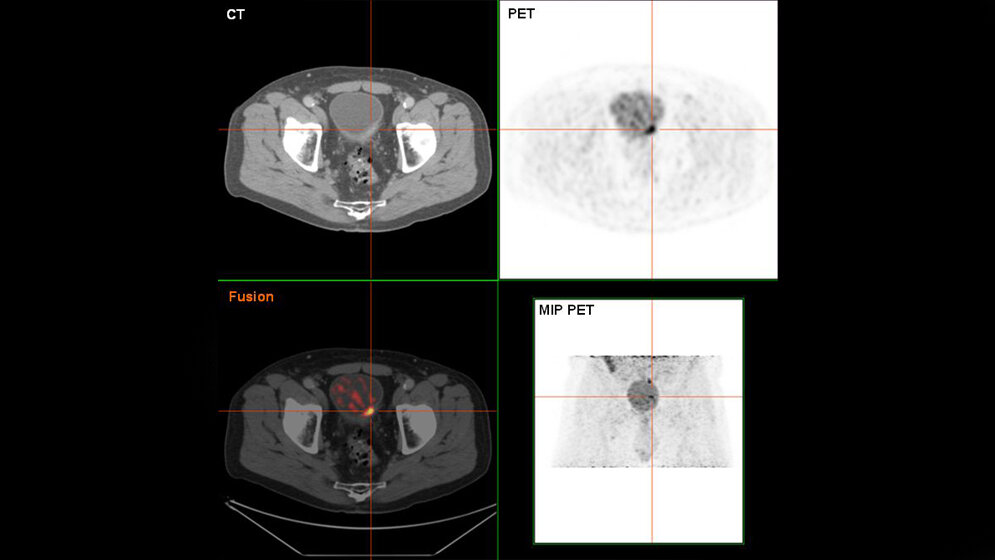

Muskel-invasive Blasenkarzinome (MIBC) machen etwa zwei Drittel der invasiven urothelialen Blasenkarzinome (UBC) aus und weisen eine hohe Morbidität und Mortalität auf. Männer sind mehr als dreimal so häufig von UBC betroffen wie Frauen.

Die FAU-Forscher haben nun herausgefunden, dass der Therapieerfolg und das Überleben dieser Patienten durch die Bestimmung der weißen Blutkörperchen, die als stromale tumorinfiltrierenden Lymphozyten (sTIL) bezeichnet werden, vorhergesagt werden können. Diese Lymphozyten werden dabei als einfacher morphologischer Parameter und als Biomarker eingesetzt: Ihre Menge und räumliche Verteilung innerhalb des Tumor-Immun-Milieus erlauben Prognosen über die Stadien der Tumorentzündung und Tumorsubtypen und helfen bei der Personalisierung der Patiententherapie. In weiteren Studien wollen sie ihre Ergebnisse nun überprüfen und die Methode weiterentwickeln.